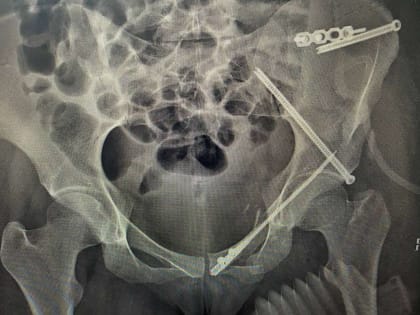

Сложная операция в Воронеже: врачи спасли жизнь молодой пациентки

Хирурги успешно провели операцию после ДТП с мотоциклом.